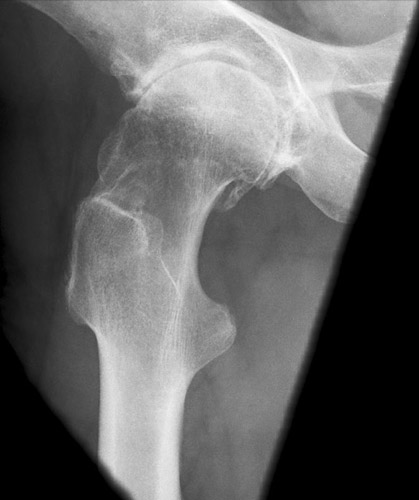

Fehler

Die obere Begrenzung des Trochanter majors reicht fasst bis zum Hüftkopf. Er überdeckt zum Teil den Schenkelhals und dessen distalen Teil. Der Trochanter minor bildet sich weit unterhalb des Trochanter major im Schaft des Oberschenkels, randbildend, ab. Der femur wurde zu weit abgespreizt. oder fast seitliche Lagerung der Oberschenkels. Nicht die Oberschenkelachse soll zur Filmachse parallel stehen, sondern die Achse des Schenkelhalses.

Abhilfe

Der Patient darf den Femur nur wenig nach außen abspreizen, damit stellt sich der Schenkelhals horizontal ein.